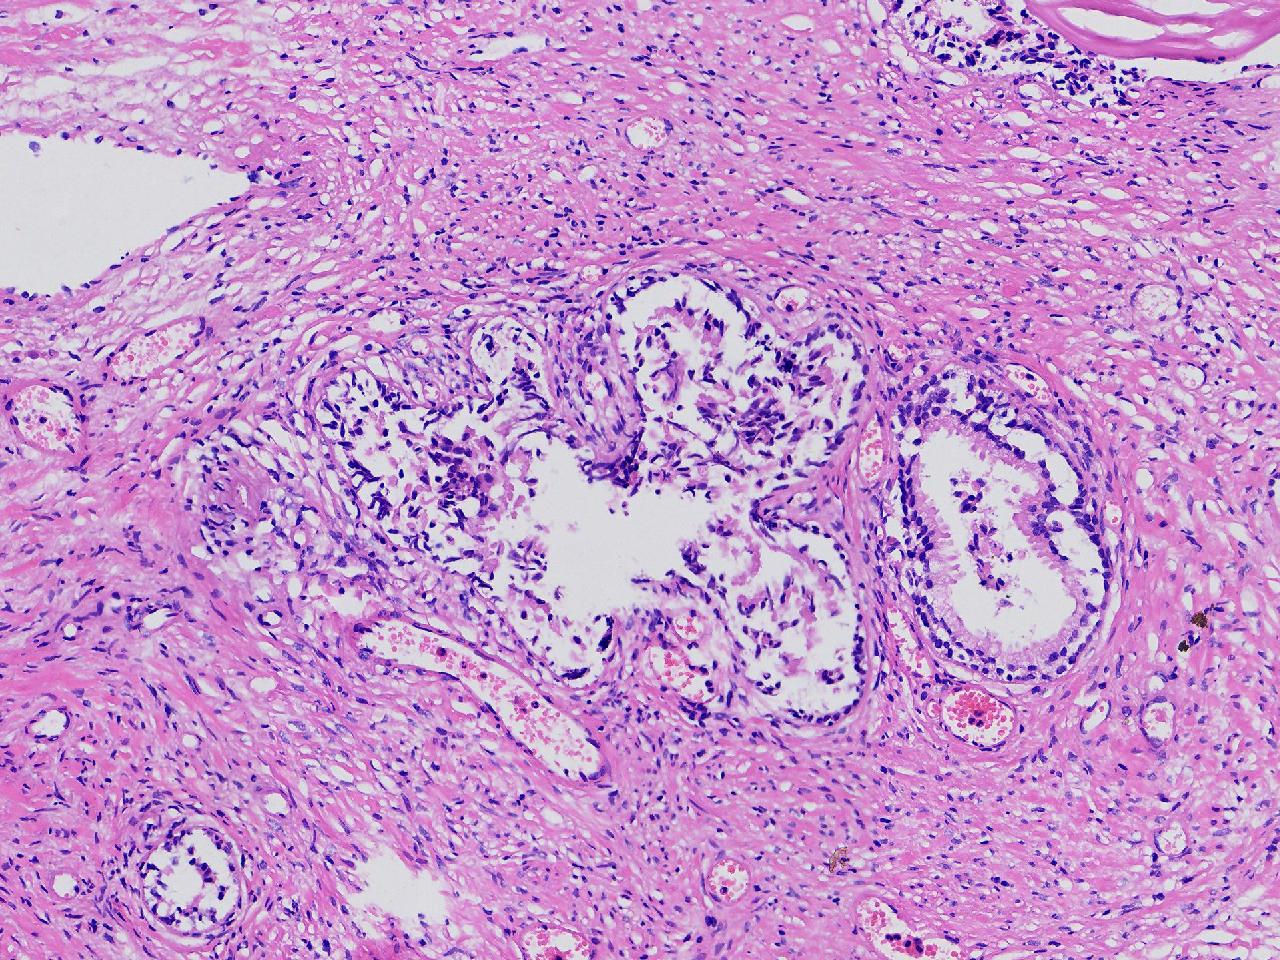

良性前列腺增生?

男,68岁,排尿困难半年余。行前列腺前切术。

前列腺电切标本

灰粉色条索状软组织多块,4X3X3厘米。

考虑为良性前列腺增生症

良性增生

BPH.